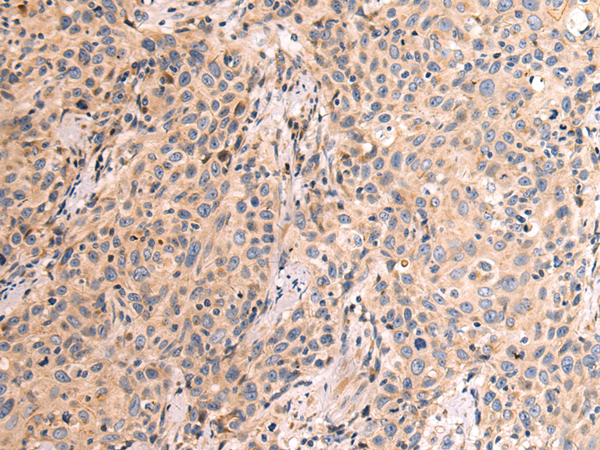

ELISA, IHC

IHC positive control:

Human prostate cancer

IHC Recommend dilution:

50-200